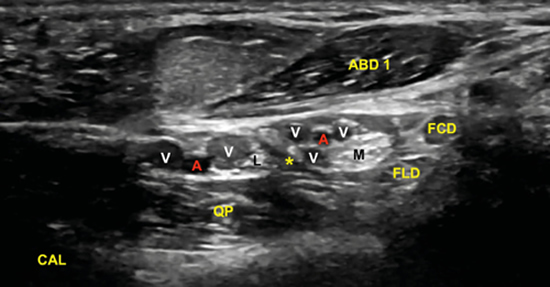

El examen para localizar la división del nervio tibial continúa desplazando la sonda en eje transverso y en sentido cráneo caudal desde la posición anterior (Figura 4) en busca del túnel del tarso distal o túnel talocalcáneo (Figura 10), donde el nervio se divide en el nervio plantar medial y nervio plantar lateral (Figura 11), 1.3 a 2.5 cm proximal a la división de la arteria tibial posterior3,9. Dellon-Mackinnon describieron la división del nervio tibial en relación al eje entre el centro del maléolo medial y la tuberosidad del calcáneo (línea Dellon-Mackinnon) (Figura 12) en un 90 % de los casos (55 % en la línea, 16 % 1 cm distal y 19 % 1 cm proximal)10. Más tarde, Moroni y cols. refieren tal división 16.4 mm proximal a dicho eje8.

Figura 11. Imagen sonográfica de la diferenciación del nervio plantar medial (M) y del nervio plantar lateral (L) debajo de la arteria y venas (A, V) y sobre el tendón flexor largo del primer dedo (FLD). En superficie el retináculo flexor (*).

No obstante, la visualización de los nervios plantar medial y plantar lateral es más evidente cuando se avanza hacia distal. Para ello se mantiene la sonda en eje corto (Figura 13) tomando como referencia la tuberosidad posterior del calcáneo, de donde parten el eje de Dellon-Mackinnon4 y el triángulo de Heimkes (área entre tuberosidad del calcáneo, el vértice del maléolo medial y el navicular)8 (Figura 12).

La imagen sonográfica se centrará en el espacio situado bajo la fascia profunda del músculo abductor del primer dedo, por donde discurrirán los haces neurovasculares plantar medial y plantar lateral, diferenciados y separados por el septo de Heimkes o interfascicular3. El nervio plantar medial se muestra con mayor sección que el nervio plantar lateral, y las venas laterales con mayor luz que las mediales (Figura 14).

Figura 14. El septo interfascicular (*) parte desde la fascia profunda del músculo abductor del primer dedo (ABD 1) hacia el tendón flexor largo del primer dedo (FLD) dividiendo la cámara superior de la cámara inferior, donde respectivamente se encuentran el haz neurovascular plantar medial (M: nervio plantar medial; A/V: arteria y venas plantar medial) y el haz neurovascular plantar lateral (L: nervio plantar lateral, A/V: arteria y venas plantar lateral). En profundidad, el músculo cuadrado plantar (QP) y la superficie del calcáneo (CAL).